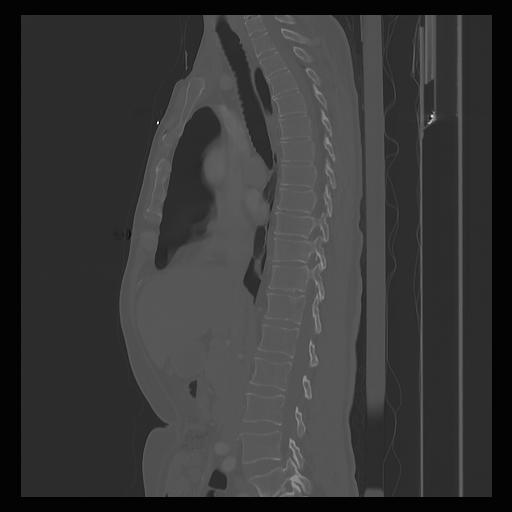

33 PULMON,CE,Sagittal,3.000,PULMON,Sagittal,